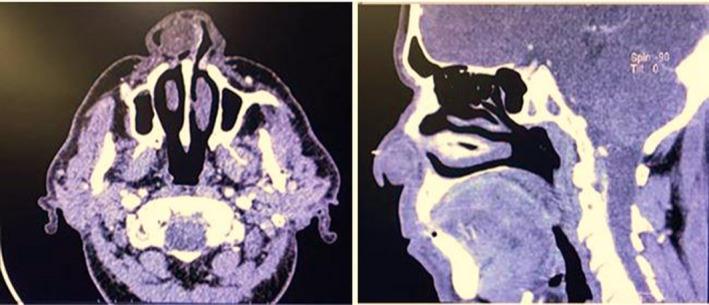

鼻侧壁神经鞘瘤:一例报告。

Schwannoma of the lateral nasal wall: A case report.

Nasal schwannomas account for about 4% of head and neck schwannomas. We report a rare case of lateral nasal wall schwannoma presenting as a nasal mass in a 70-year-old man.

摘要

鼻神经鞘瘤约占头颈部神经鞘瘤的4%。我们报告一例罕见的外侧鼻壁神经鞘瘤病例,该病例表现为一名70岁男性的鼻腔肿物。